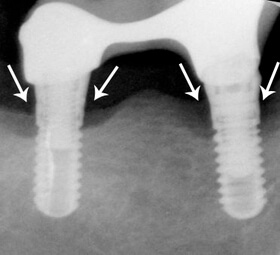

Féléves kontroll felvétel a regeneratív műtét után. A csontkráter kitelődött csonttal, azaz a defektus meggyógyult